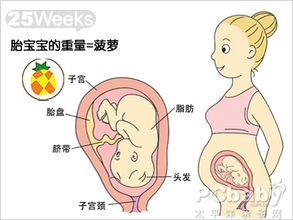

怀孕25周胎教 怀孕二十五周 怀孕25周胎儿图25周胎动注意事项 第二人生

怀孕25周 怀孕25周注意事项 怀孕25周胎儿图 怀孕第七个月胎儿图 怀孕计算器

懷孕25周的胎兒是什麼樣子 附 胎兒每周發育標準參考表 壹讀

懷孕25周胎寶寶是怎麼樣的呢 孕婦要注意什麼呢 看完很喜人 壹讀

懷孕期第25週 寶寶階段發展 Superbaby

懷孕第25週 Mamaway媽媽餵懷孕哺乳育兒百科

孕25周 胎宝宝大脑飞速发育

懷孕25周胎寶寶是怎麼樣的呢 孕婦要注意什麼呢 看完很喜人 壹讀

懷孕25周的胎兒是什麼樣子 附 胎兒每周發育標準參考表 每日頭條